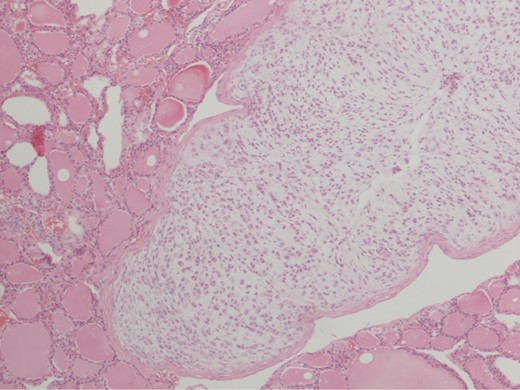

Histologic evaluation revealed high-grade chondrosarcoma originating from the cricoid cartilage, with local invasion of the surrounding right lobe of thyroid gland (Fig. 2). Tumour was present at one margin in the external thyroid muscle. There was no tumour present in the oesophagus.

Pathological specimen showing high-grade chondrosarcoma invading into surrounding right lobe of thyroid gland using hematoxylin and eosin stain under ×10 magnification.